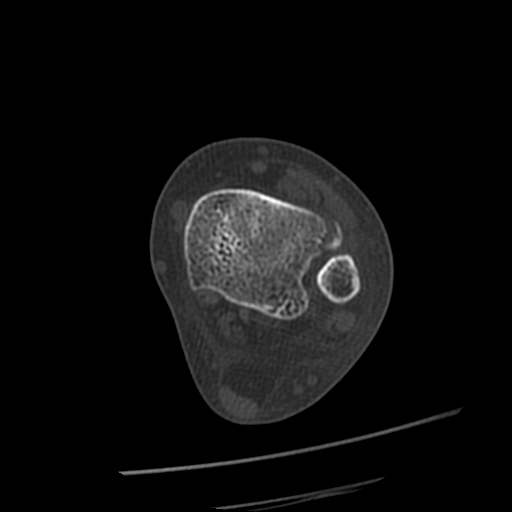

CT : avulsion fracture of distal tibia at distal tibiofibulat ligament insertion.

short leg splint with crutch gait